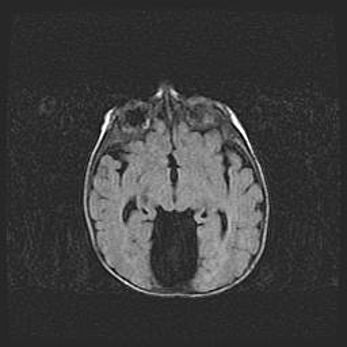

Неполная лизэнцефалия (пахигирия). Открытая гидроцефалия.

Возраст: 17 дней

Вес: 3110 г

Пол: мужской

Окружность головы: 33,5 см

Срок гестации: 35-36 недель

Лизэнцефалия—недоразвитие корковой пластинки и мозговых извилин в результате нарушения миграции нейронов коры. Поверхность мозговых полушарий гладкая. Микроскопически выявляется отсутствие нормальных слоев коры и скопление групп нейронов в подкорковом белом веществе.

Пахигирия—уменьшение числа вторичных извилин. В пораженном полушарии нервные клетки образуют толстый недифференцированный слой с неправильно расположенными нервными волокнами и группами гетеротопных клеток. Нервные клетки незрелые. Белое вещество истончено. При этом нередко аномально развит корково-спинномозговой путь.